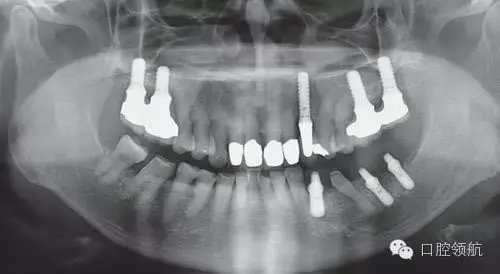

利用曲面斷層及CBCT檢查埋入部位情況,雖未出現(xiàn)與主訴相關(guān)的神經(jīng)損傷,但無意中卻發(fā)現(xiàn)了種植體的舌側(cè)穿孔(圖1、圖2)。

圖1 術(shù)后的曲面斷層影像。